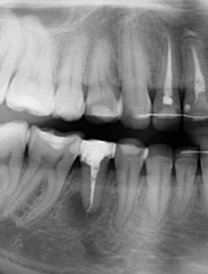

Возможно ли удалить кисту без потери зуба? Какова вероятность, что она не появится снова?

В некоторых случаях зуб удается спасти после адекватного эндодонтического лечения.

Возможно, стоит обратиться к врачу стоматологу-терапевту и побороться за зуб.